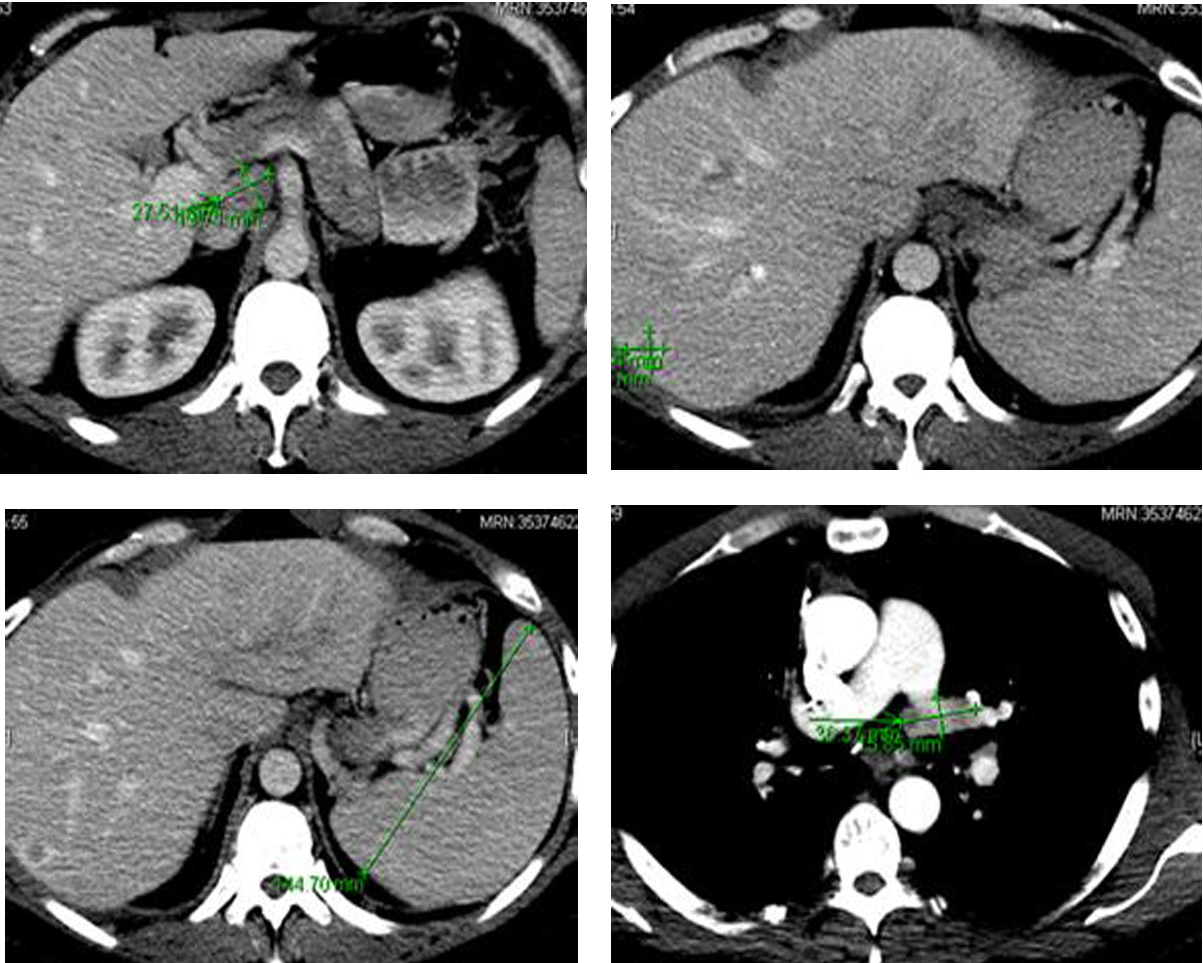

Following the surgery, in March 2013, patient developed multiple episodes of pancreatitis (waxing and waning). Endoscopic ultrasound revealed multiple metastatic lesions in the pancreas (3 mm in head, 2 mm and 3 mm in neck and 1 mm in tail) and the liver. Multiple enlarged lymph nodes, especially at the level of porta hepatis, were also noted (Fig. 6). Fine needle aspiration of these lesions confirmed malignant cells consistent with medullary thyroid carcinoma. Gastroenterology was consulted and two pancreatic stents were inserted.

![]() Click for large image | Figure 6. Computer tomography of the abdomen showing several hepatic metastasis, splenomegaly and abdominal adenopathy. |